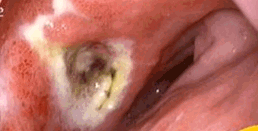

Right Photos are my arteries and are links, yikes! What does artery disease look like on a CTA? A 2017 CTA photo of my arteries: The left photo unfortunately shows the current disease in the CFX artery. My recent radiological report from these photos mentions coronary artery disease only and depicts the stenosis within the artery as a percentage, mine is < 25% great, but this is only a guesstimate and can vary 10% 20% and up to 30% is my understanding. I have seen two cardiologists since with the radiological report and they both say great less than 25%, blockage while neither actually even bothered to look at the photo with the actually disease. I asked both doc's if they would like to see the photos and they both declined. The Stenosis reported in the above angio photo group (BEFORE / AFTER) at the time of the stent was reported as 40% 50% and 60% by angio cath and now by CTA they say < 25%, I am in the process of finding out by comparison if this is true, I will be comparing the 2013 CTA to the 2017 CTA. By observation I noticed the overall sublumenal disease show in photos has not seemed to change much if at all. I also learned that the angio photo guesstimates are just that and do not hold much weight as far a accuracy if at all, they appear to be visual guides with numbers attached by the surgeon and or helper at the time of the CATH, why bother except to sell more operations. So in 2013 my artery blockages were 40-50-60% determined by the angiogram now compared to a CTA they are less than 25%, yea right, wishful thinking for sure. The disease looks the same to me photos to be posted. Can't help thinking that they do many unnecessary by pass operations based on the CATH readings/photos which are at best only guesstimates in most cases. i.e. I recently had a friend diagnosed by CATH that he had 80% blockages is all four arteries and received an immediate quadruple by bass operation? When you go under you basically give them cart blanche to do what is necessary, the way I got around this was to get the CTA before the CATH, In my case I was pretty sure what was going to happen before the CATH.

In the above left photo white is calcified plaque, dark irregularities and raised areas are the disease itself . Of note: although the stenosis, narrowing is only 25% this give or take 10% -30%, yes. in most cases it is reported that the stable white plaque is not the soft vulnerable plaque that causes a heart attacks but instead its the dark areas of soft vulnerable plaque beneath the artery walls that tend to be the culprits, however they actually can occur anywhere at anytime. The idea is that through (positive remodeling) the plaque builds up pressure beneath the artery wall and finally when enough pressure or disease happens within, the area is subject to rupture. If the artery blockage us severe enough a heart attack can ensue. So passing all your basic yearly tests really don't mean a thing buddy, imaging is key! |